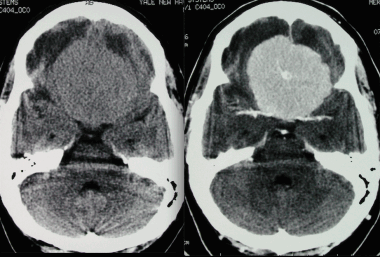

Менингиома лобной доли: КТ-картина. После введения контрастного вещества виден характерный вид «колеса со спицами» в структуре слабо контрастируемой опухоли. Несмотря на то, что данный паттерн чаще наблюдается при ангиографии, он также отмечается на томографических изображениях.

МРТ того же пациента, выполненная после предыдущей КТ: аксиальное Т1-взвешенное изображение после введения гадолиния и аксиальное Т2-взвешенное изображение. Видна крупная менингиома лобной области, расположенная срединно, со специфическим паттерном «колеса со спицами».